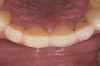

Figure 4  Preoperative smile view.

Figure 4